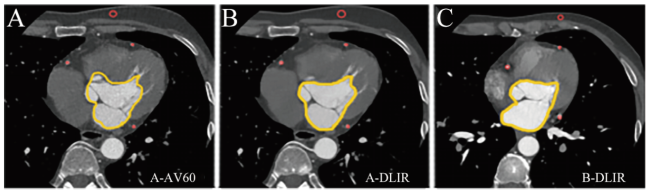

2名放射科医师主观图像质量评价有较强的一致性(Kappa=0.926,P < 0.001)。B-DLIR主观图像质量平均分高于A-AV60(P < 0.05),但低于A-DLIR(P < 0.05)。A-DLIR与B-DLIR的清晰度、伪影、小分支可见度比较差异均无统计学意义(P均>0.05),见表4图3

图3 A-AV60、A-DLIR、B-DLIR 3种方案CCTA的主观图像质量评分对比箱线图

注:A-AV60评分最低,A-DLIR略高于B-DLIR,综合独立因素的得分,B-DLIR图像质量不弱于A-DLIR。

Figure 3 Comparison boxplot of subjective image quality scores of CCTA with three schemes: A-AV60, A-DLIR and B-DLIR